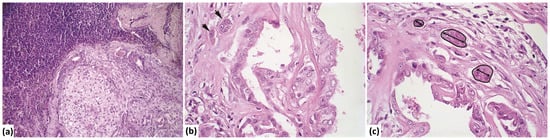

2.3. Histology

2.4. Histomorphometry of Invasive Areas

3.2. Evaluation of Size, Perimeter, and Number of Invasion Foci